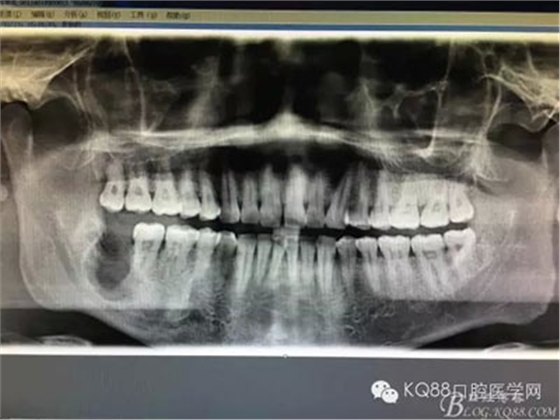

患者、常xx、男、26歲,主訴:右側(cè)下頜牙床腫痛不適數(shù)月。??茩z查:48未見(jiàn)萌出,頰側(cè)骨質(zhì)略有膨隆。捫診輕微不適,無(wú)乒乓感,牙齦色澤基本正常,探針無(wú)盲袋。全景片檢查:48埋伏水平阻生,其牙冠下方有一囊性陰影,界限清楚,大小約1.5x1.1cm。CBCT檢查:囊性病變已經(jīng)導(dǎo)致部分頰舌側(cè)骨板缺失。診斷:48埋伏阻生伴發(fā)囊性變。治療計(jì)劃:建議拔除48,并摘除下方的囊腫?;颊咄庵委熡?jì)劃,簽知情同意書。

圖3.這張重建的全景片,似乎48就漂浮在囊腔上方,由此感覺(jué)48拔除如同探囊取物一般。

圖18.術(shù)后全景片影像檢查:頰舌側(cè)骨缺損接近下頜神經(jīng)管,會(huì)不會(huì)出現(xiàn)骨折的可能,有點(diǎn)糾結(jié)??!